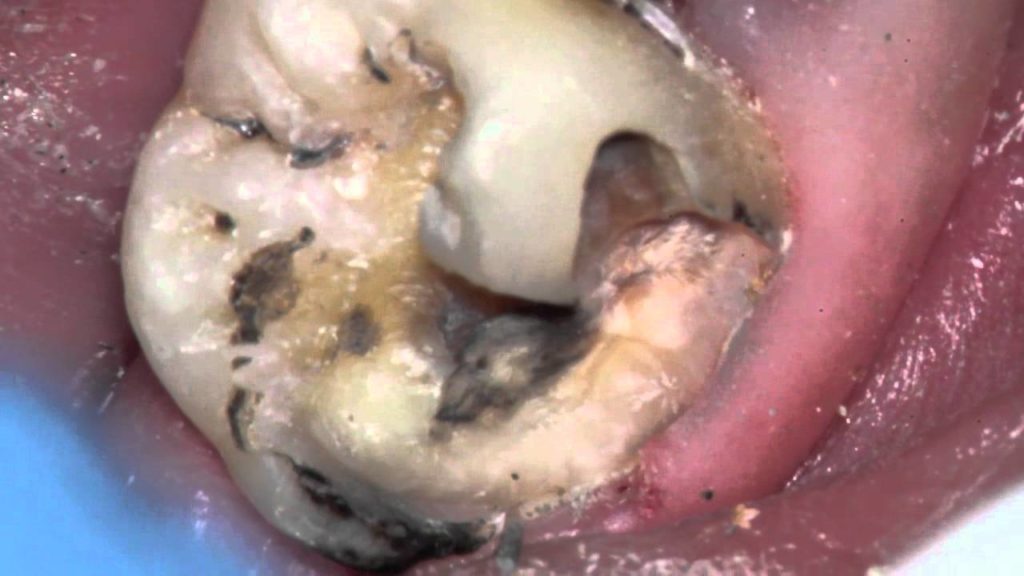

home Procedures Monster cavity under filling- Can tooth be saved? Monster cavity under filling- Can tooth be saved? By dentists Posted in Procedures Posted on April 22, 2017